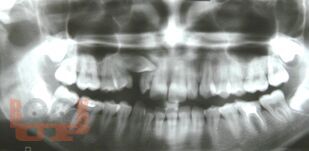

В пособии на современном уровне подробно изложены вопросы эпидемиологии, этиологии ретенированных зубов, особенности клинической картины этой аномалии. Особое внимание уделено диагностике и лечению данной патологии.

Представлены тестовые задания и ситуационные задачи с эталонами ответов. В пособии представлены авторские фотографии пациентов.